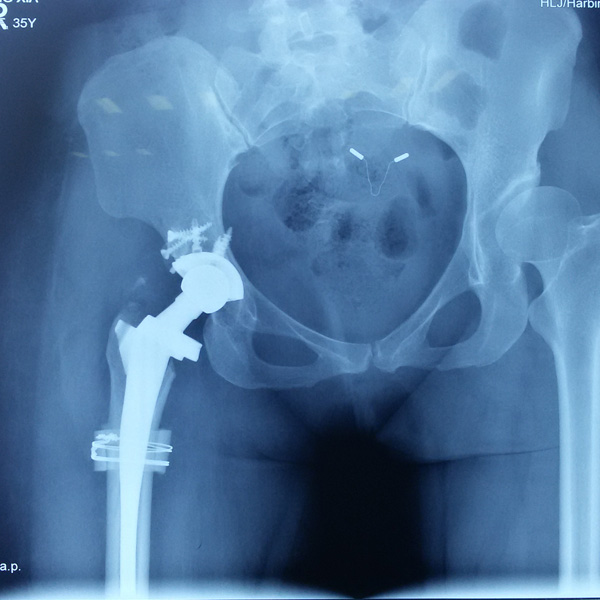

先天性髖關節脫位

患者王某某,女,41歲,從會走路以來就發現一條腿長,一條腿短,也就是人們俗稱的“跛子”,之前雖然兩條腿長短不一,但起碼還可以走路,維......